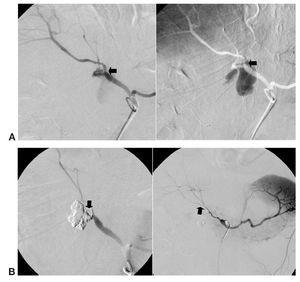

Once lesiones fueron roturas arteriales con formación de pseudoaneurisma de una arteria musculoesquelética (fig. 1) y 9 fueron lesiones en una arteria visceral (fig. 2), 4 de las cuales fueron lesiones de la arteria gastroduodenal (fig. 3), tres secundarias a complicaciones de una duodenopancreatectomía cefálica y otra a una punción directa con un catéter de drenaje 10 french de un absceso secundario a una colecistectomía.

Fig. 3. (A) (caso 3). Extravasación de sangre por arteria gastroduodenal en paciente con fístula pancreática secundaria a duodenopancreatectomía cefálica, con pérdida de la sutura quirúrgica (flecha). (B) Oclusión con onyx 34 del muñón arterial y del pseudoaneurisma (flecha hacia abajo), estando conservada la vascularización hepática inicial (flecha hacia arriba).

El caso 4 se intentó resolver 24 horas antes con la colocación de una prótesis cubierta en la arteria hepática, que no se consiguió posicionar por la angulación del nacimiento del tronco celíaco que impedía su progresión. En ese momento se colocaron 3 coils electrolargables de platino en la arteria hepática común (GDC, Boston. Natick, USA). Dado que se mantenía la situación de inestabilidad hemodinámica del enfermo se repitió la angiografía, que demostró persistencia del sangrado. Por ello, decidimos cerrar la arteria inyectando Onyx 34 sobre los coils, con un resultado efectivo inmediato.

En el caso 4 intentamos colocar una prótesis cubierta, y no lo conseguimos por problemas técnicos en la flexibilidad del material para adaptarse a la curvatura del tronco celíaco. Este problema, en nuestra opinión, es bastante frecuente y limita la utilización de estos dispositivos. Ante esta circunstancia se colocaron coils electrolargables sobre la arteria hepática derecha y en el nacimiento de la arteria gastroduodenal, no siendo oclusivos y manteniéndose el sangrado. A las 24 horas, con el enfermo hemodinámicamente inestable, decidimos elegir un agente embolizante líquido, denso y no adhesivo, que pudiéramos colocar entre los coils, lo que realizamos con 0,3 cc de onyx 34, con un resultado oclusivo inmediato. Esto nos ocurrió también en el caso 16, en el que habíamos colocado previamente coils que no consiguieron cerrar totalmente el pseudoaneurisma, manteniéndose el sangrado.